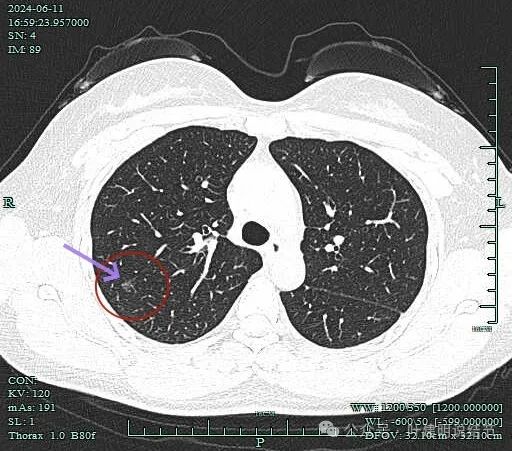

病灶虽小,但毛刺明显,而且天蓝色箭头所指的邻近血管有弯向病灶侧。

连续部分也是混合密度。

上图层面有磨玻璃成分,实性成分已经开始减少而不明显。但整体轮廓与瘤肺边界较清。

最边缘处磨玻璃密度,并有细毛刺样征。